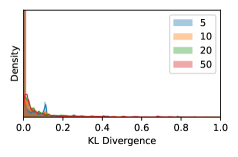

5.1 Distribution of Uncertainty Scores

Distribution of Uncertainty Scores Across Different Severity Levels As explained in Section 3, each uncertainty metric essentially defines an order/ranking among the data points. We conducted an analysis to better understand what data will be assigned high uncertainty under a particular uncertainty metric . Picking out the highest ranked data points (), we calculated the ratio of data points from each SL. Figure 4 summarizes the results as box plots for the Kaggle-DR and the Messidor-2 datasets; additional detailed statistics can be found in Table S.1 in the supplementary materials. From the plot and table, SL1 & SL2 examples account for a higher proportion among the top-ranked uncertain examples across the three ensemble methods. This finding matches our intuition that incipient disease examples (SL1 & SL2) are more likely to be considered uncertain by ensemble methods due to their ambiguity.

In contrast, the MC-dropout method showed the worst overall performance among the three, as it can be seen from the high ratios of SL0 examples among the uncertain negatives in Figure 4. The histograms in Figure 2 provides another perspective to look into the phenomenon, where a decent proportion of MC-dropout model’s predictions on SL0 inputs entailed low confidence (far from 0 or 1), which from another angle explained why MC-dropout was less specific in terms of lower FNP; many no-DR inputs (i.e. SL0) were erroneously assigned high uncertainty by MC-dropout models.

As discussed in Section 5.1 and Section 5.3 in the main paper, the mean metric and the stacking ensemble will have better performance in the precision (specificity) on the ambiguous data. Here, more detailed results are shown in Figures S.3 & S.6 and Table S.1. Figures S.3 & S.4 show the histograms of the uncertainty score for Kaggle-DR and Messidor-2 datasets that are the in-distribution (i.d.) dataset in our experiment and FigureS.5 & S.6 show the histograms for ImageNet and CIFAR-10 datasets, which is the o.o.d. datasets in our experiment. Each group of histograms contains results from the three evaluated ensemble methods (stacking ensemble, MC-dropout and TTA) and the three uncertainty metrics (mean, var and kl). Additional detailed results not displayed in Figure 4 can be found in Table S.1, which shows the proportion of the data of different SLs varies across different . For comparison, we also included in Table S.1 the results from single learners, and the proportions of data of different SLs (before any selection was made).